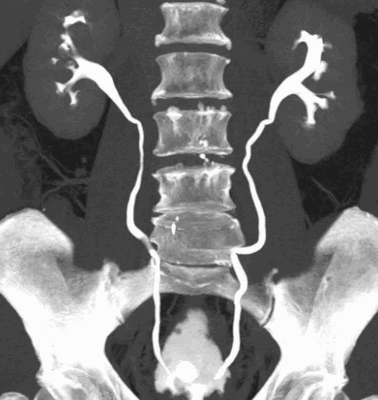

КТ органов мочевыводящей системы с усилением

Контрастирование требуется не всегда, введение препарата необходимо при:

проведении комплексного урологического исследования - КТ мочевыводящих путей показывает функцию каждой почки в отдельности, препятствие к оттоку урины на любом уровне, патологические рефлюксы, кисты и пр.